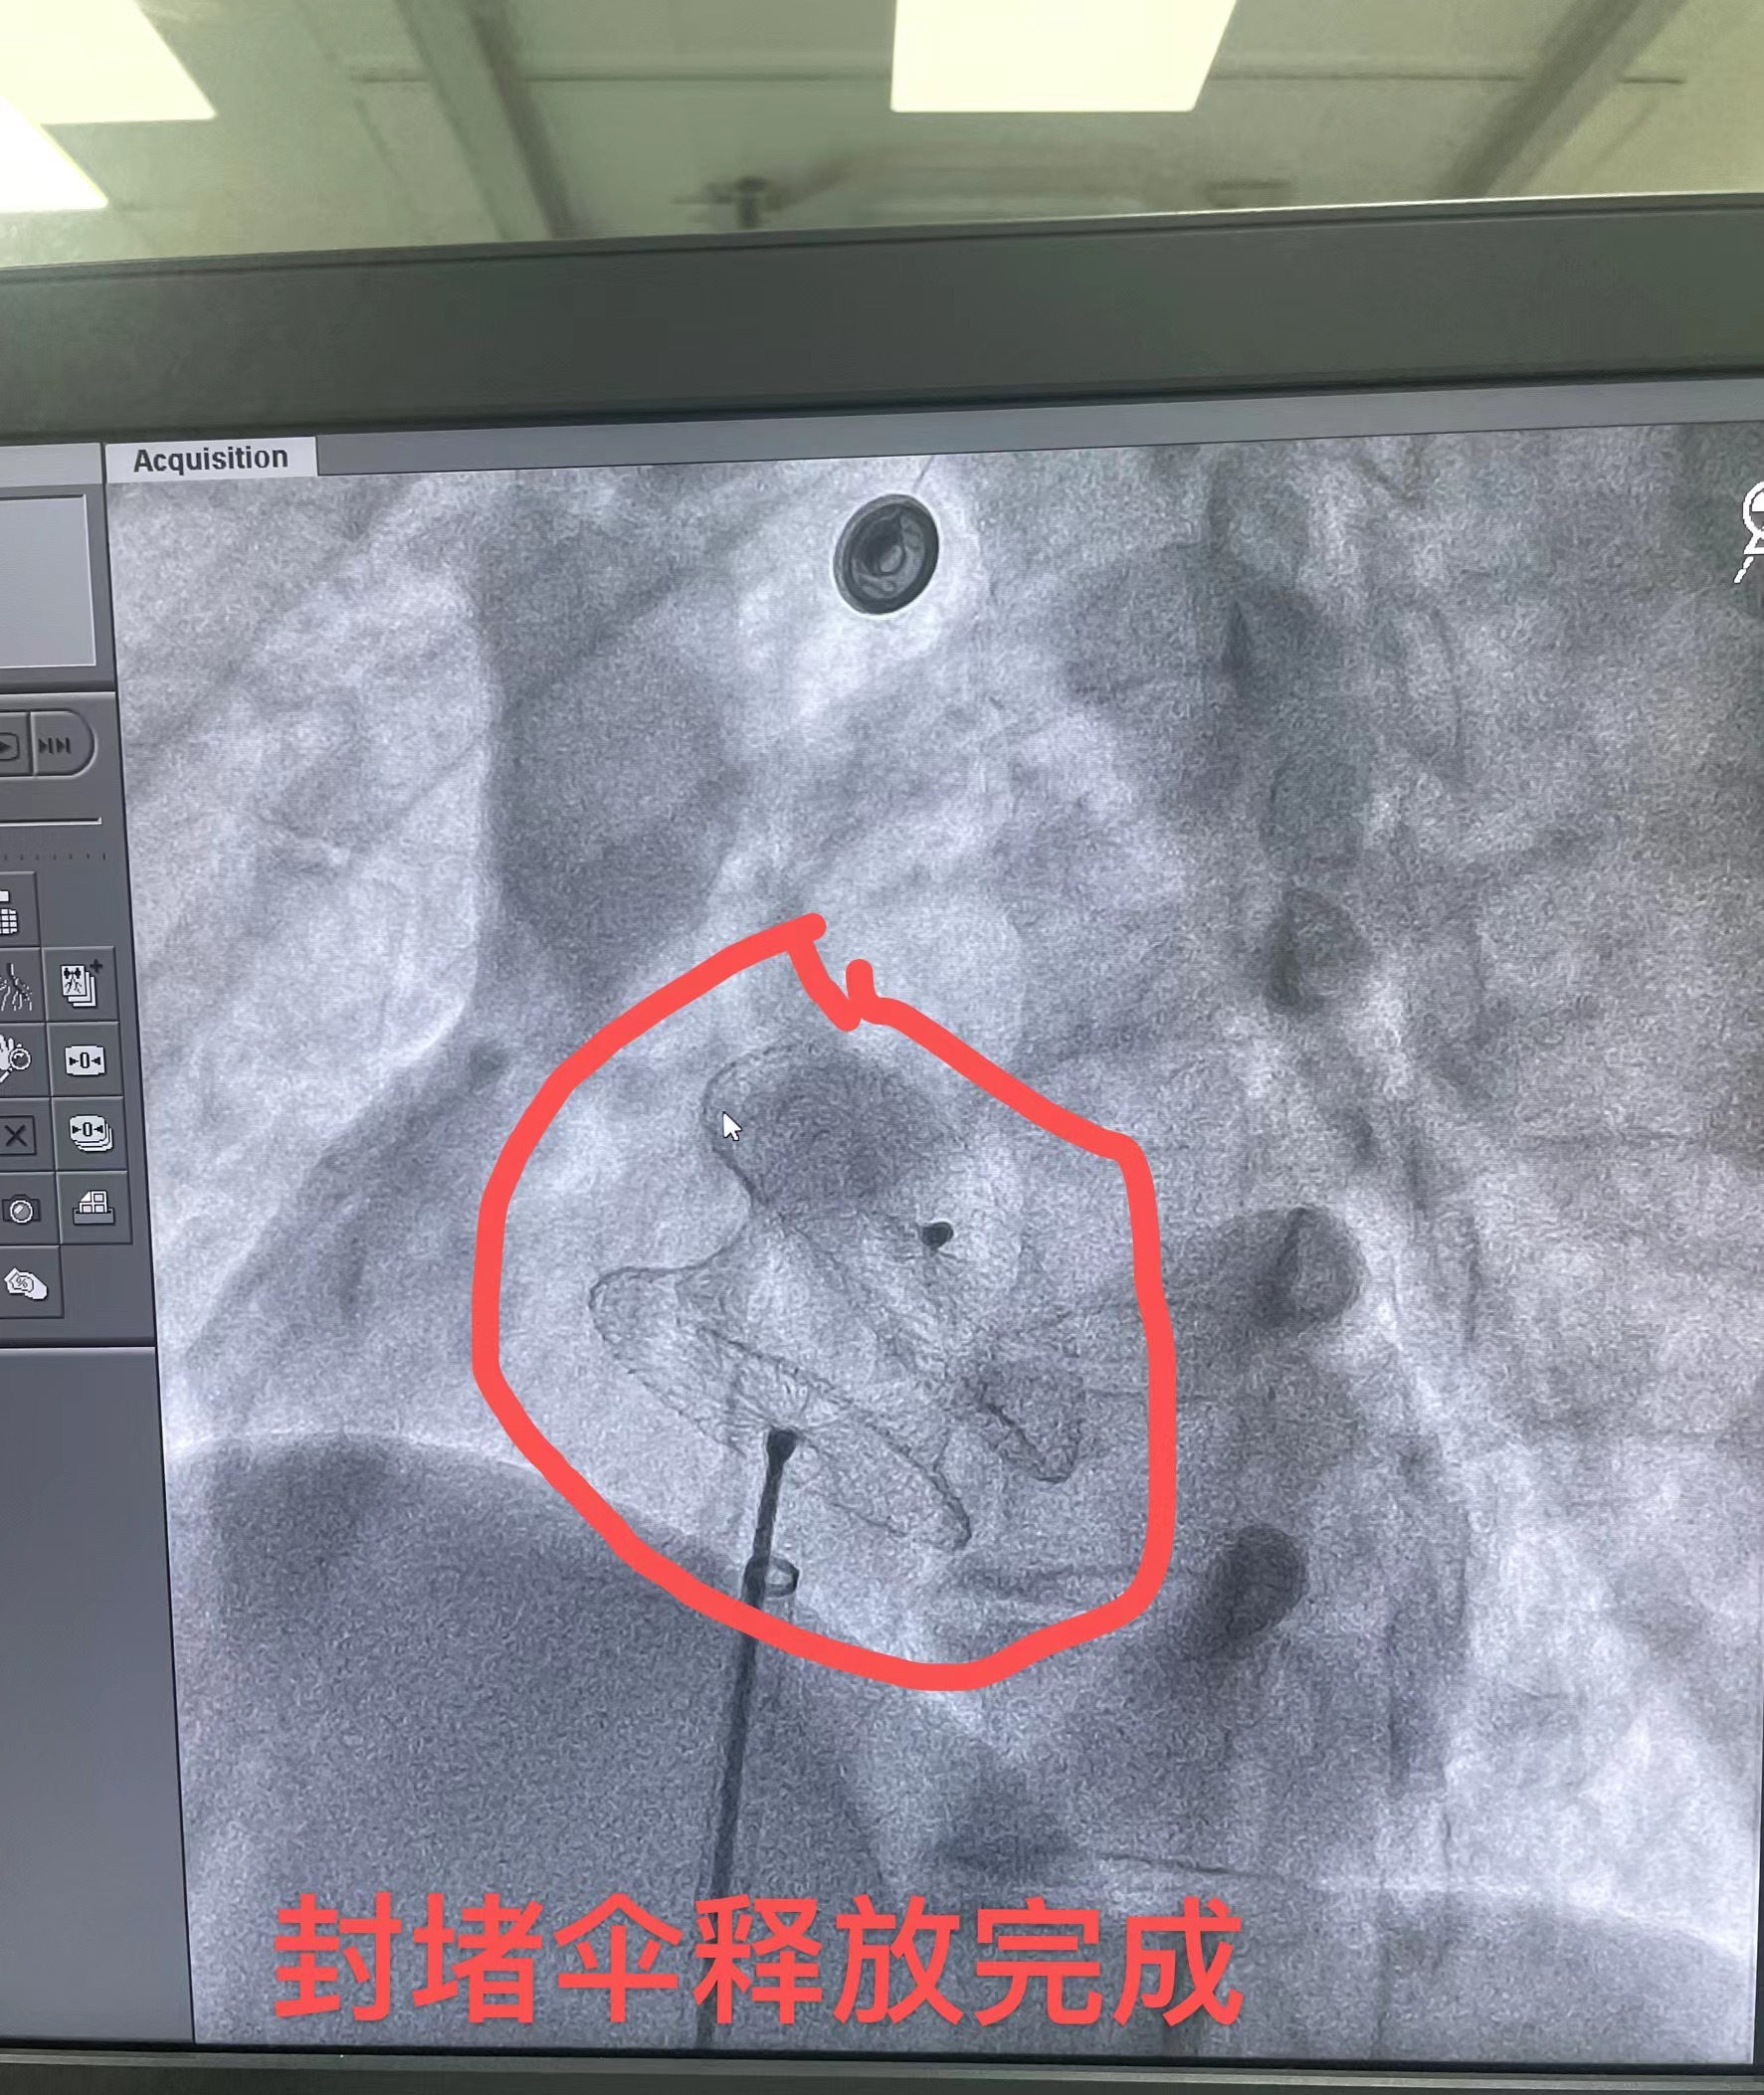

在与患者做好充分的术前准备后,由张曹进主任及李勇主任、黄生华主治医师进行介入手术,心血管内科团队互相配合,术中局部麻醉,从大腿根部的股静脉做一个穿刺,仅在患者身上切开一小道的伤口,由此引入封堵器装置,在透视下及超声检查下证实房间隔缺损封堵器位置良好,房缺完全封堵,无残余分流。手术仅半小时,就顺利完成手术,术后患者转入CCU监护治疗。

李勇主任表示,房间隔封堵术采用经股静脉穿刺的办法,将封堵伞片送至心房,修补位于左右心房间的缺损处,阻断心房水平的左向右分流,恢复正常的血液循环。相较于房间隔修补术,房间隔封堵术其优点是创口小,痛苦小,恢复快,避开了开胸、体外循环、心脏停跳等环节,手术全程由超声引导,实时了解心脏情况,判断手术效果,手术成功率高,现已广泛成熟应用于临床,房间隔缺损、室间隔缺损、动脉导管未闭等先天心脏疾病,均可以采取介入封堵方式治疗。

房间隔缺损封堵术示意图